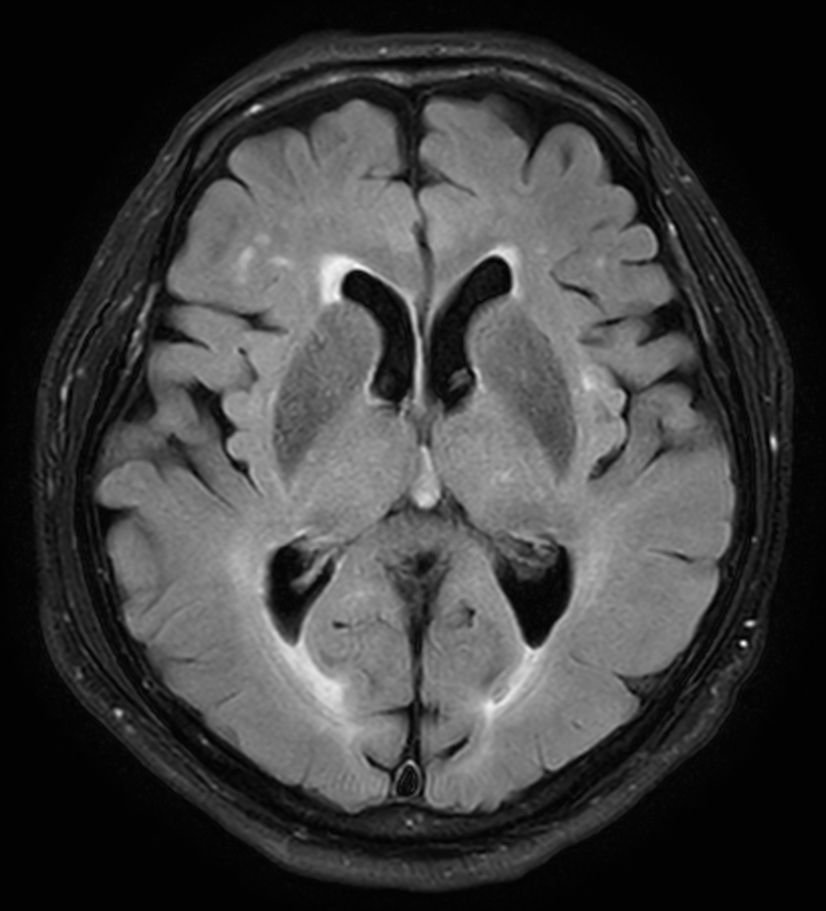

뇌 MRI(Magnetic Resonance Imaging)는 강한 자기장과 라디오파를 이용해 뇌의 구조와 기능을 고해상도로 촬영하는 영상검사입니다. 방사선을 사용하지 않으며, 연부조직 표현력이 뛰어나 뇌신경계 질환의 조기 진단에 매우 효과적입니다.

뇌 MRI로 진단 가능한 주요 질환

- 뇌종양: 위치, 크기, 성질 확인

- 뇌출혈 및 뇌경색: 허혈성 및 출혈성 병변 확인

- 치매: 뇌 위축 및 혈류 감소 확인

- 다발성경화증: 신경계 염증성 질환 진단

- 기형 및 낭종: 선천적 구조 이상 확인

- 뇌동맥류: 필요 시 조영제 활용해 혈관 촬영 가능